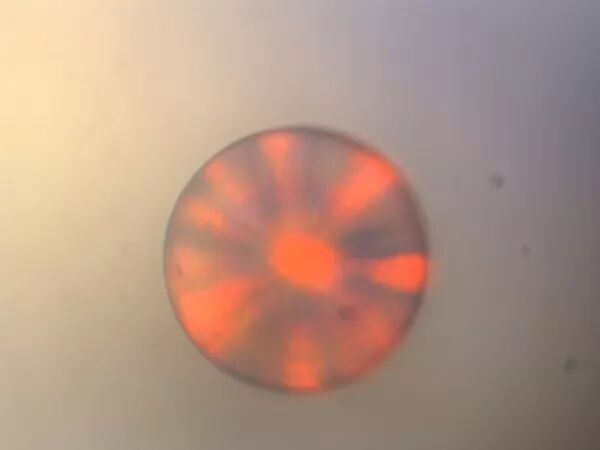

“你看过蝴蝶的翅膀吗?”当常宁像个小姑娘一样跟别人聊起这个话题时,她想说的其实是一个世界级生物原理,“蝴蝶翅膀的绚丽颜色来自于‘结构性色彩’,这种色彩通过周期性结构材料(即光子晶体)对光的反射、透射等进行高效的调控,相较于色素性色彩,拥有极高的稳定性。”

“滴血验癌”一直是医学界研究的重难点。就在刚结束的第三届中国“互联网+”大学生创新创业大赛中,东南大学MxHealth团队的癌症早期精准检测系统正是运用了光子晶体微球技术,设计出一款自动化检测仪,通过一滴血,就可完成12项癌症的早期筛检,摘得大赛“银奖”,引起了业界关注。

该检测系统的核心、“光子晶体微球”就成了最精准的“癌症尺子”。

据东南大学生物电子学国家重点实验室副主任、常宁博士的导师赵祥伟介绍,实际上该实验室已经研究光子晶体微球多年,“检测的原理是:利用不同排列方式的光子晶体组成不同颜色的微球,并连接相应的肿瘤抗体,再将它们嵌在芯片的网格上;当血液流过时,血液中的肿瘤标志物就会被相应的抗体抓获;随后和荧光标记的第二抗体结合,形成了一种‘三明治’结构,通过图像分析和数据处理能获取癌症检测结果。”